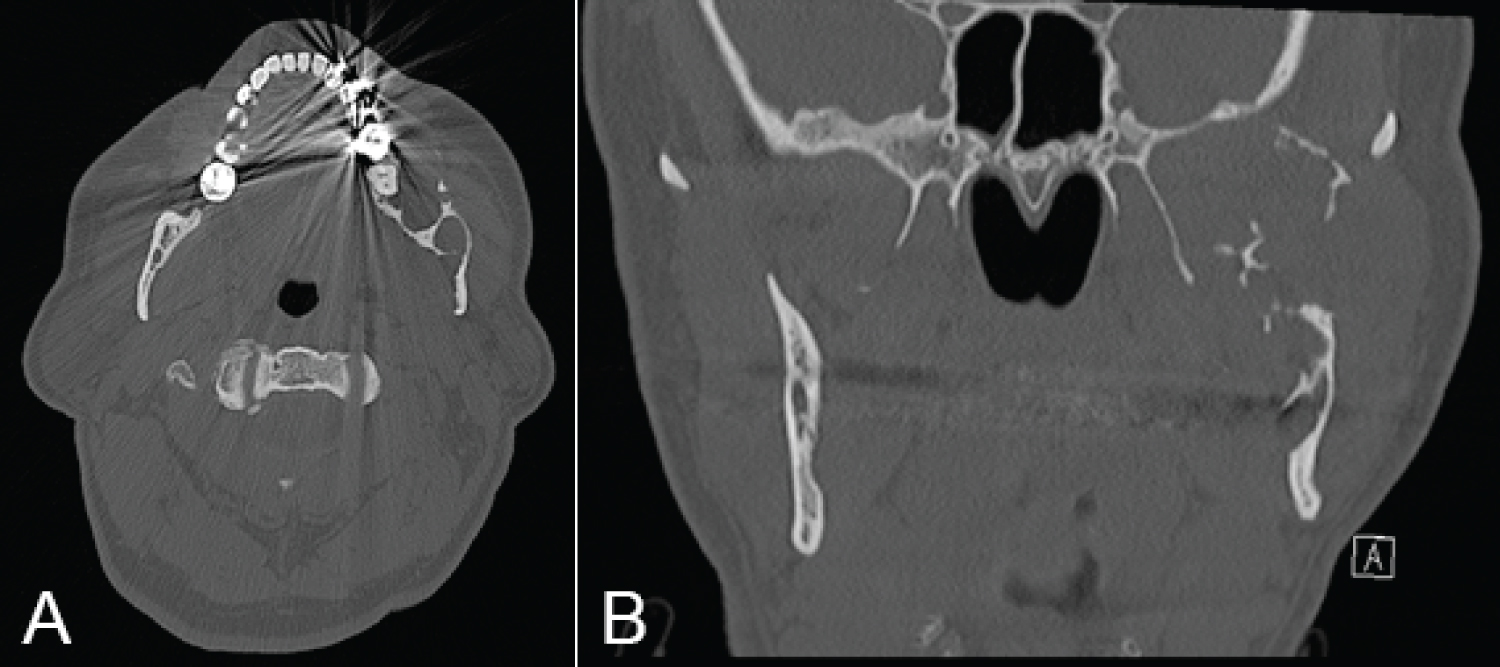

At three weeks post-operatively he noted weakness in his left marginal mandibular branch of facial nerve and a maximal mouth opening of 25 mm. He was advised to continue a puree diet for six weeks, at which point he started to upgrade his diet as tolerated. Six months post-operative CT demonstrated good positioning of prosthesis and no evidence of recurrence (Figure 10). Eight months post-operative MRI showed no sign of residual or recurrent tumour. At one year post-surgery his maximal mouth opening had improved to 30 mm and he had ongoing House-Brackmann grade II left marginal mandibular nerve weakness.

Figure 10: Six months post-operative CT (A) Lateral view; (B) Front view. View Figure 10